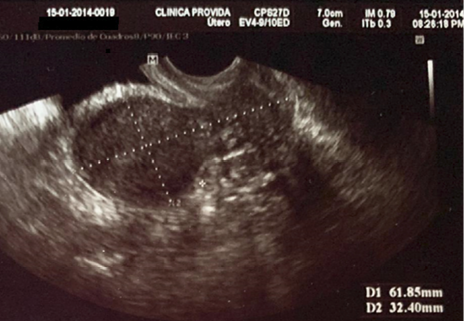

Antecedentes patológicos personales: incompetencia cervical, más aborto recurrente. Se observa la longitud cervical y longitud de útero previo al primer cerclaje en la Figura 1 y 2. Antecedentes quirúrgicos: cerclaje cervical por vía vaginal en la tercera gesta. Antecedentes gineco-obstétricos: menarquia 12 años, ciclos menstruales regulares, duración de 6 días, sangrado moderado. Gestas 4, partos 0, abortos 3, cesáreas 0, hijos vivos 0.

G1: aborto a las 20 semanas de gestación. G2: aborto a las 20 semanas de gestación. G3: aborto a las 21 semanas de gestación a pesar de haberse realizado cerclaje vaginal técnica McDonald a las 12 semanas por el servicio de ginecología-obstetricia del Hospital Básico Provida; se observa en la Figura 3 los hilos del cerclaje con la protrusión de membranas ovulares en vagina el día del aborto. G4: actual, edad gestacional 13 semanas por fecha de ultima menstruación (FUM).